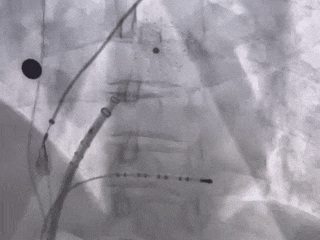

MemoLefort封堵器展开后DSA下充分评估

肝位即刻造影,位置合适,上下缘无造影剂漏

牵拉试验,牵拉后有明显回弹,位置无移动

展开后DSA下造影,观察封堵左心耳开口无残余分流,且封堵器放置位置理想,充盈整个心耳开口处。肝位牵拉有回弹,无任何相关位移。